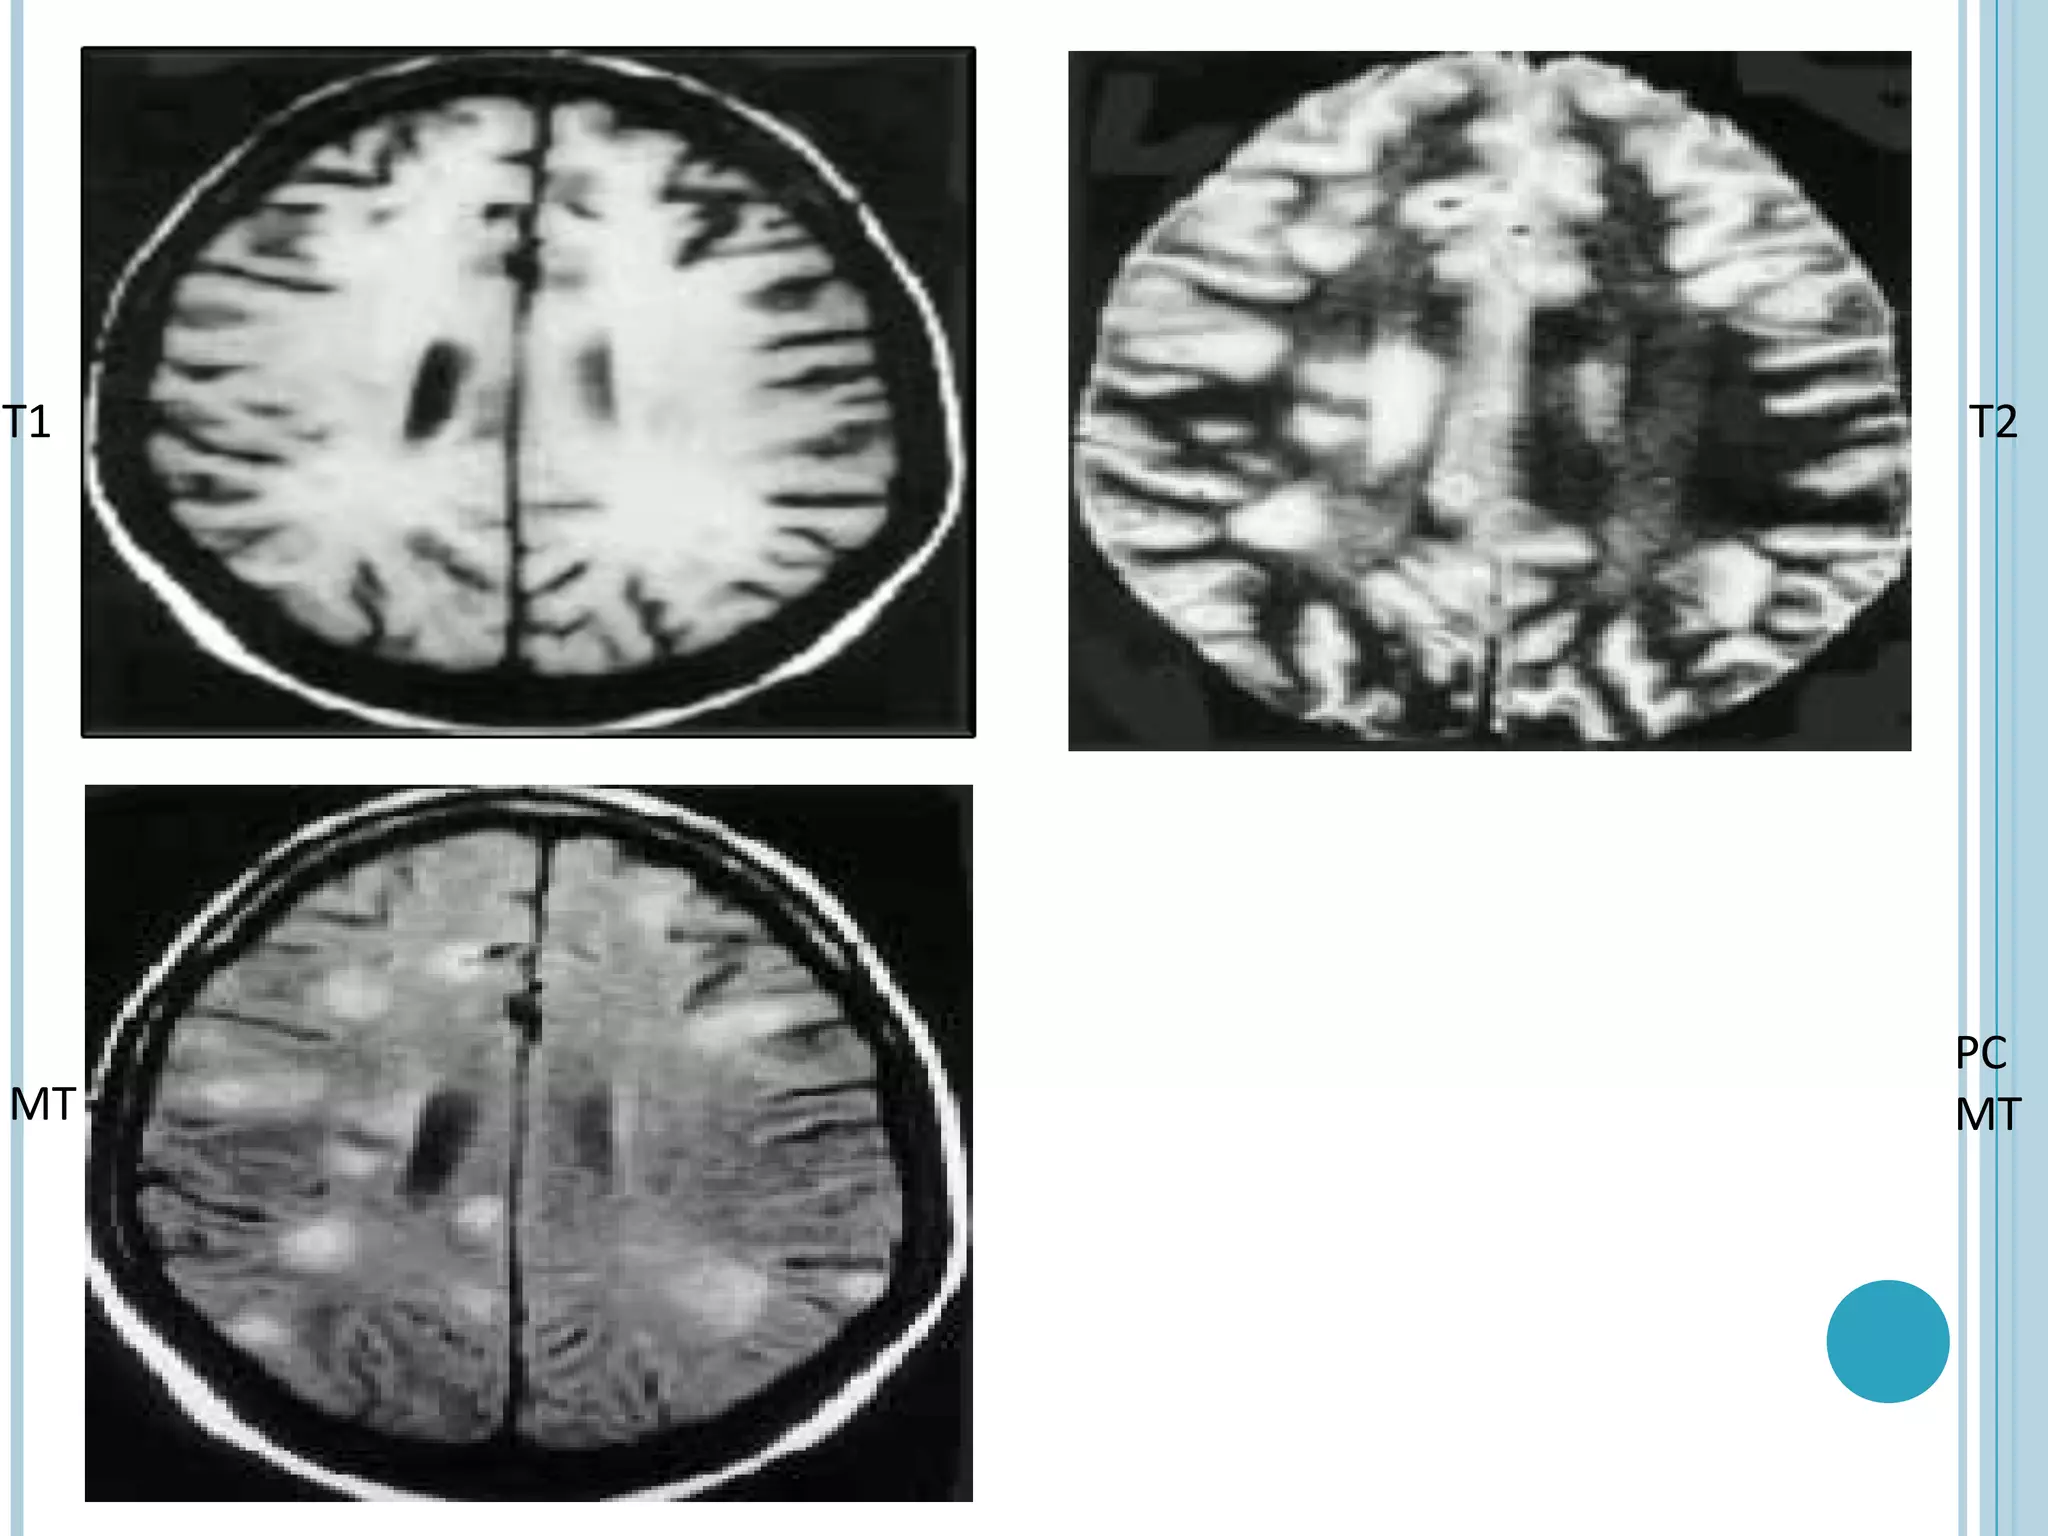

T1   T2

PC

MT   MT

TUBERCULOMA

•   Pre-contrast T1-W MT imaging helps to better assess the disease load in CNS

tuberculosis by improving the detectability of the lesions, with more number

of tuberculomas detected on pre-contrast MT images compared to routine SE

images

•   It may also be possible to differentiate T2 hypo intense tuberculoma from T2

hypo intense cysticerus granuloma with the use of MTR, as cysticercus

granulomas show significantly higher MT ratio compared to tuberculomas